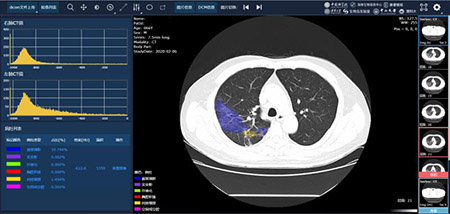

智慧篩查、診斷及重症預測;據張康教授介紹,該系統基於五十萬份臨床影像學大數據,運用深度學習、遷移學習、語義分割等多種人工智慧前沿技術,而開發的基於胸部CT和X-ray的新冠肺炎AI輔助診斷系統。相比人工閱片,該系統有三大優勢。首先是快速、準確地診斷新冠肺炎。據悉,有經驗的影像科醫生閱完一個患者的胸部CT圖像尚需約15至20分鐘,而該AI系統則可在20秒內完成檢測及診斷過程,且診斷準確率達90%以上,相當於一個省級三甲醫院影像學副教授的診斷水準。其次,該系統還具有病情嚴重程度分級和重症危重症預測功能,可對胸部CT圖像每一層面的小結節、磨玻璃影和實變進行自動識別、標註及定量分析,可通過患者的吸氧頻率、血氧飽和度、酸鹼平衡、肝功能、凝血功能等,綜合預測病人發展為重症、危重症的概率和時間,有利醫生及時干預,降低患者死亡率。

定量計算指導用藥;該系統還能夠協助醫務人員進行藥物效果評估,指導用藥,包括對同一位患者用藥前後的CT圖像對比分析,通過定量計算病人在用藥前後的變化,判別藥物是否有效,指導臨床用藥。